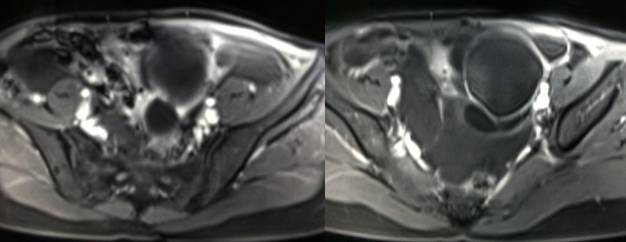

MR检查:

病理结果:黄体血肿

黄体血肿为正常排卵过程中,卵泡层破裂,引起出血,较多的血液潴留在卵泡或黄体腔内形成血肿。

正常黄体直径为15mm左右,以后转变为白体,并在下一个周期的卵泡期自然消退。若黄体内出血量较多,则形成黄体血肿,或称黄体内出血,出血性黄体。黄体血肿多为单侧,一般直径为40mm,偶可达100mm,黄体血肿被吸收后可导致黄体囊肿,较大的血肿破裂时可出现腹腔内出血,剧烈腹痛、少量阴道流血和腹膜刺激征,不易与宫外孕区别。

根据时间不同MR信号也有所不同,TIWI脂肪抑制序列可以鉴别脂肪和出血。